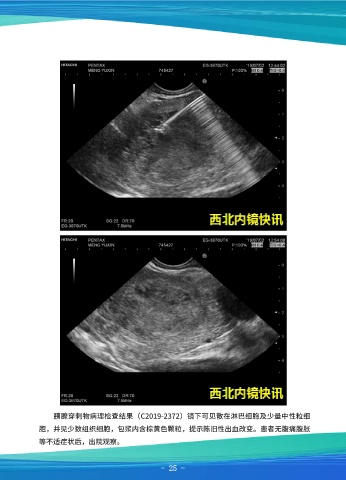

胰腺穿刺物病理检查结果(C2019-2372)镜下可见散在淋巴细胞及少量中性粒细

胞,并见少数组织细胞,包浆内含棕黄色颗粒,提示陈旧性出血改变。患者无腹痛腹胀

等不适症状后,出院观察。